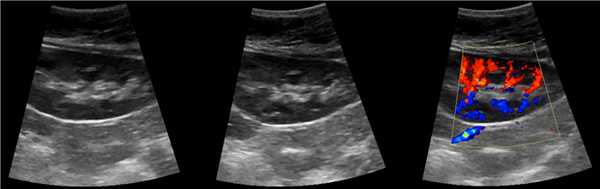

В марте 2002 г. в связи с эпизодом лейкоцитурии лечился у нефролога; при контрольном УЗИ впервые диагностированы изменения в мочевом пузыре и паравезикально слева. При повторном УЗИ выявлено (рис. 1а): правая почка увеличена в размерах (длина 12,7см; толщина паренхимы 1,6 см); чашечно-лоханочная система не расширена. Левая почка отсутствует. Стенки мочевого пузыря не изменены; в просвете слева определяется округлое образование 3,5 x 4,6 x 5,0 см с неоднородным содержимым (объем около 40 мл). Заключение: аплазия левой почки; уретероцеле слева.

а) Эхограмма.

Компьютерная томография (КТ): в проекции устья левого мочеточника и на фоне мочевого пузыря слева определяется дополнительная тень 3,1 x 4,0 x 4,0 см с четкими контурами и плотной стенкой. Мочеточник выше устья расширен до 1 см. Заключение: КТ-картина уретероцеле слева, уретерэктазия слева (рис. 1 б, в).